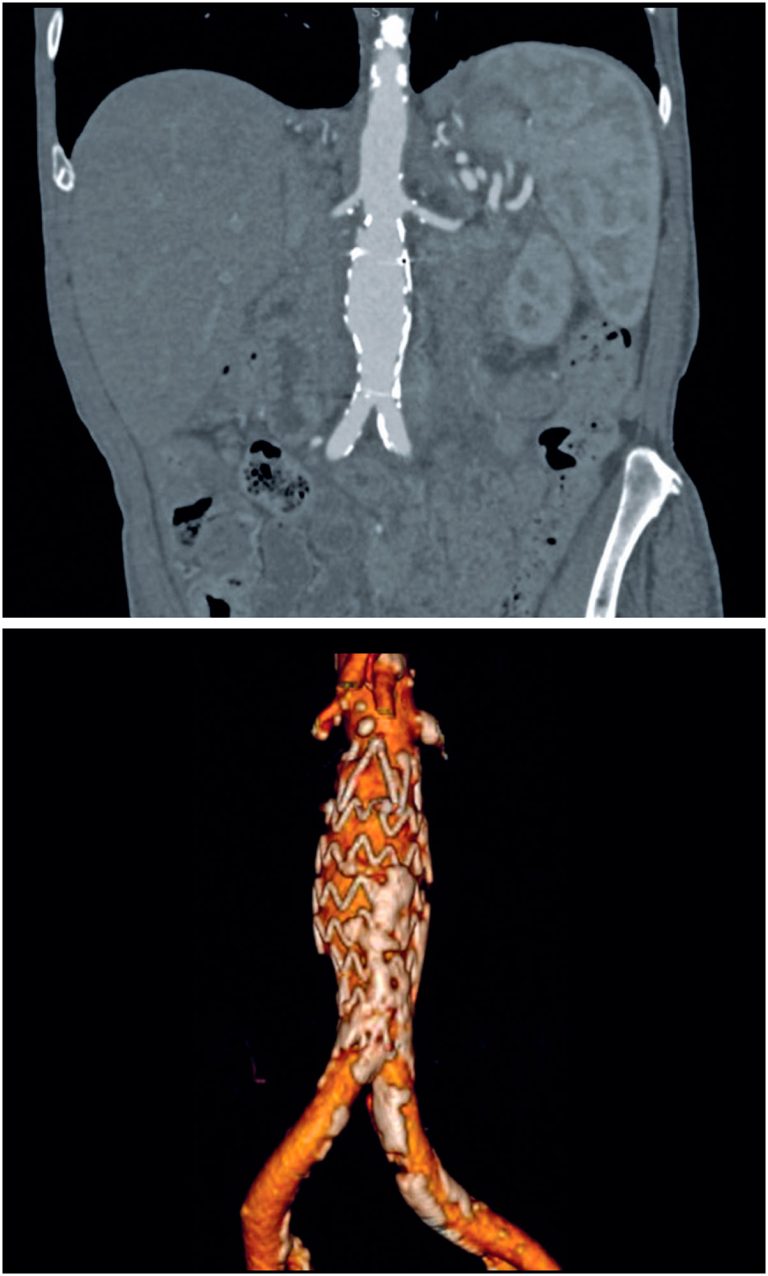

Chronic spontaneous non-aneurysmal aortic rupture treated with endovascular surgery

DOI: 10.31744/einstein_journal/2024RC1113

ABSTRACT Spontaneous non-aneurysmal aortic rupture is rare and is usually attributed to penetrating aortic ulcers, infections, tumor infiltrations, or inflammatory and collagen diseases. Chronic rupture is infrequent but extremely rare in non-aneurysmal aortas, which makes diagnosis difficult because the absence of an aneurysm can mislead the physician to rule out rupture. Here, we describe the case of an 85-year-old male, who was undergoing oncological investigation for weight loss, inappetence, and back pain. Computed tomography and magnetic resonance imaging performed 3 […]

Keywords: Aged, 80 and over; Aneurysm; Aneurysm, false; Angiography; Aorta, abdominal; Endovascular procedures; Intensive care units; Magnetic resonance imaging; Patient discharge; Penetrating atherosclerotic ulcer; Prostheses and implants; Rupture; spontaneous; Tomography, x-ray computed